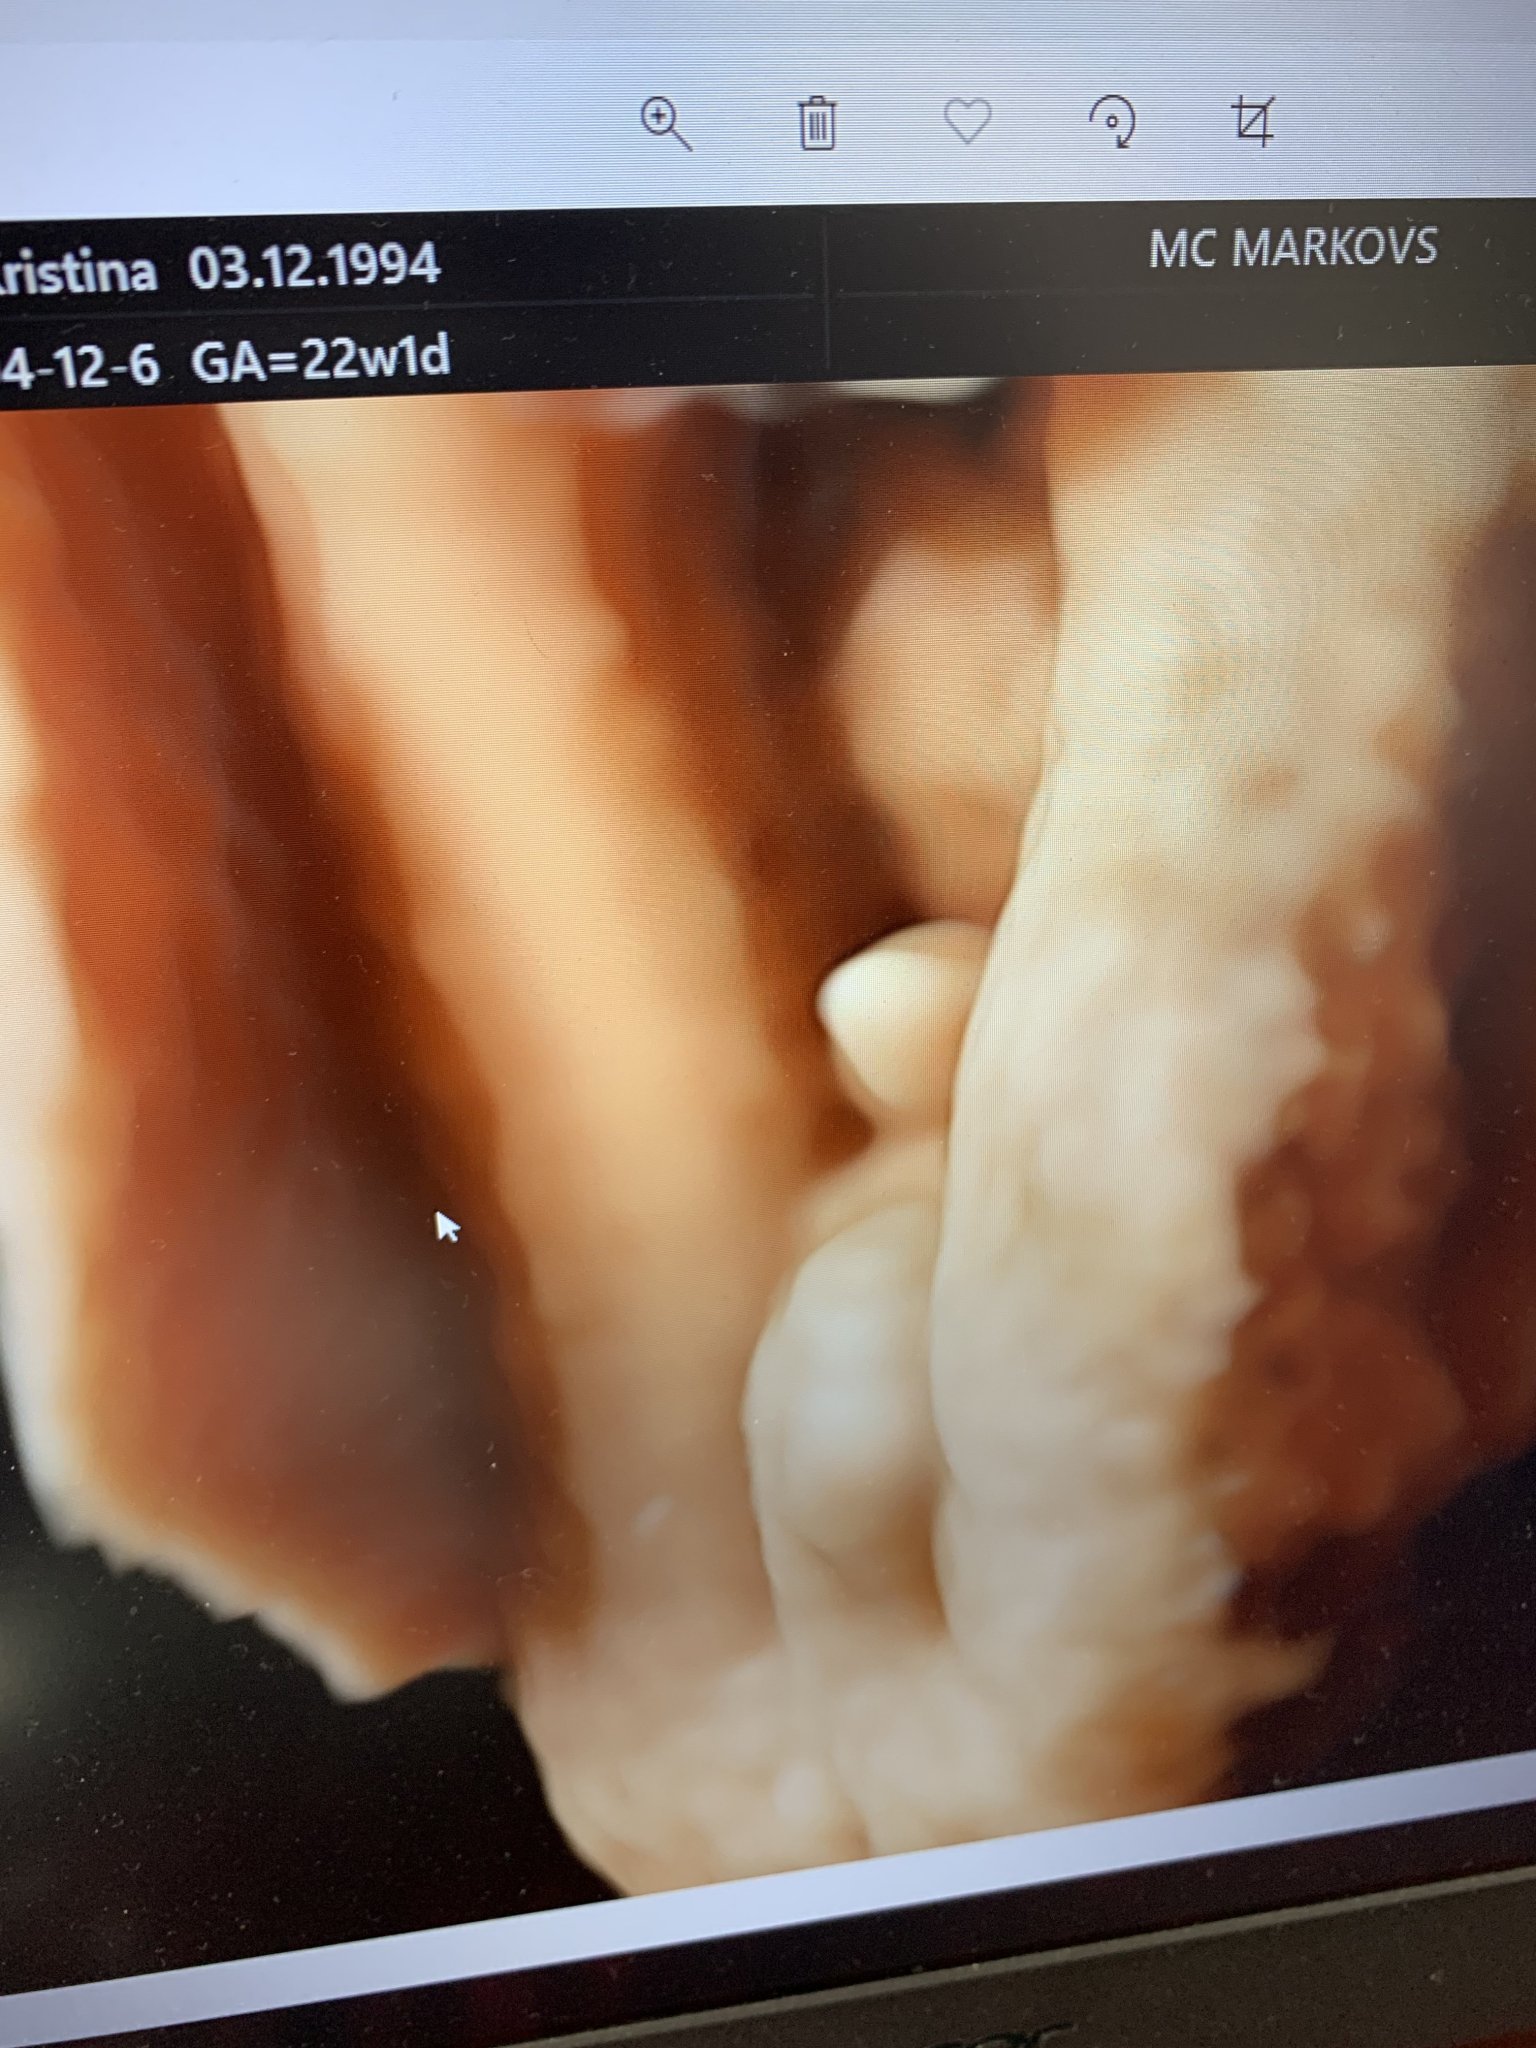

Здравейте, мамаситас. Аз съм нова тук, но съм с термин 15.08.2021г. Тук като е по-анонимно реших да си задам въпроса. На 12.04 бях на втора фм при проф. Марков(в 22 г.с) Той ми каза, че със сигурност ще имам момче и ми направи снимка... Но нали знаете как някои хора са си леко злобнички. Има една жена, която е приятелка на свекървата ми и тя вярва в някакви суеверия. Изчисляваше ми според последния ми цикъл(щяло да е момиче), сложи ми сол на главата и аз съм се почесала по устата( пак значело момиче). Когато я видях реших да ѝ се похваля, че ще е момче, защото ние с мъжа ми от самото начало се молим да е момче. И тя започна "да, да и на съседката ми така ѝ казваха до последно пък си има 20 годишно момиче вече" ... Реших да ѝ покажа снимката за да ѝ докажа и тя се обърна и ми каза, че това не ѝ приличало на пишка... Развали ми кефа тази жена и после пък и почнах да го мисля. Разглеждах в интернет за снимки на момчета, но не съм на 100% сигурна, защото нашата снимка е от друг ъгъл. Та идвам да попитам на вас как ви изглежда и случвало ли ви се е Проф. Марков да ви обърка пола? Извинявам се за дългия пост и благодаря за отговорите предварително!